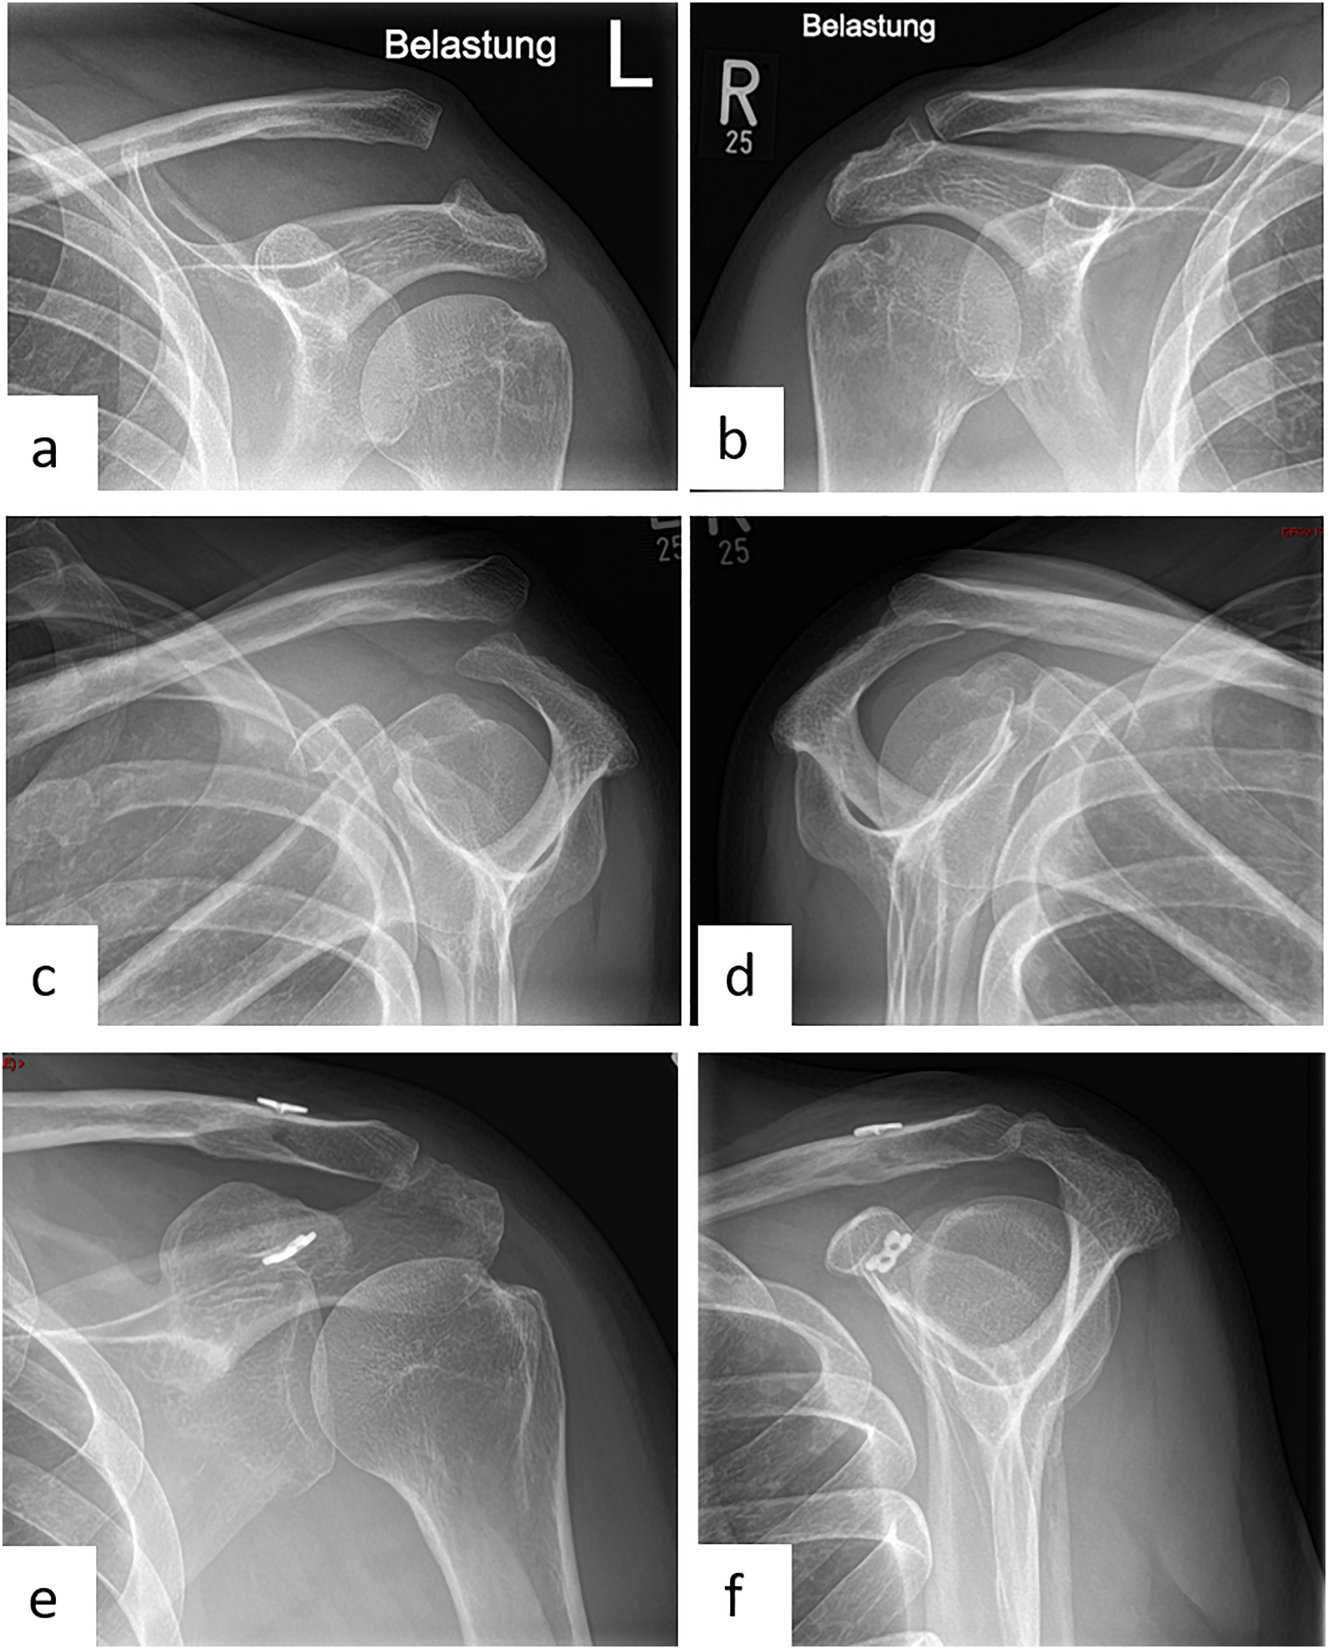

The implantation of a reverse total shoulder arthroplasty (Figure 3) represents an efficacious treatment option for those cases when a joint-preserving treatment or the implantation of an anatomic fracture prosthesis (e.g., preexisting lesions of the rotator cuff muscles, comminution zone in the area of the tuberosities, osteoporotic bone quality, concomitant fractures of the glenoid) is expected to result in poor clinical outcomes [15, 37]. In general, the two main advantages of a reverse total shoulder arthroplasty, are, on the one hand, its independence from the state of the rotator cuff muscles thanks to shifting the glenohumeral center of rotation and thus relying on the deltoid muscle to particularly initiate the shoulder abduction. On the other hand, the second advantage is its independence from the tuberosities and in particular from their anatomic reconstruction as well as their osseous healing. Clinical studies have recently reported considerable enhancement in activity and quality of life succeeding a successful implantation of a reverse shoulder arthroplasty [20, 37, 38].

Female patient (83 y), right shoulder, varus distracted 4-part proximal humerus fracture (preoperative X-ray and (3D-) CT-scan: a – a.p., b – axial, c – sagittal, d – 3D-CT-reconstruction, e – coronal), implantation of a reverse total shoulder arthroplasty (postoperative X-ray: f – a.p.).